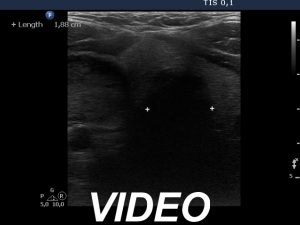

Ultrasonography. The thyroid was echonormal. There was a hypoechoic nodule in the right lobe. The dimensions of the nodule were 39x21x42 mm, width, depth and length, respectively. The lesion had a partial halo and both perinodular and intranodular vascularity.